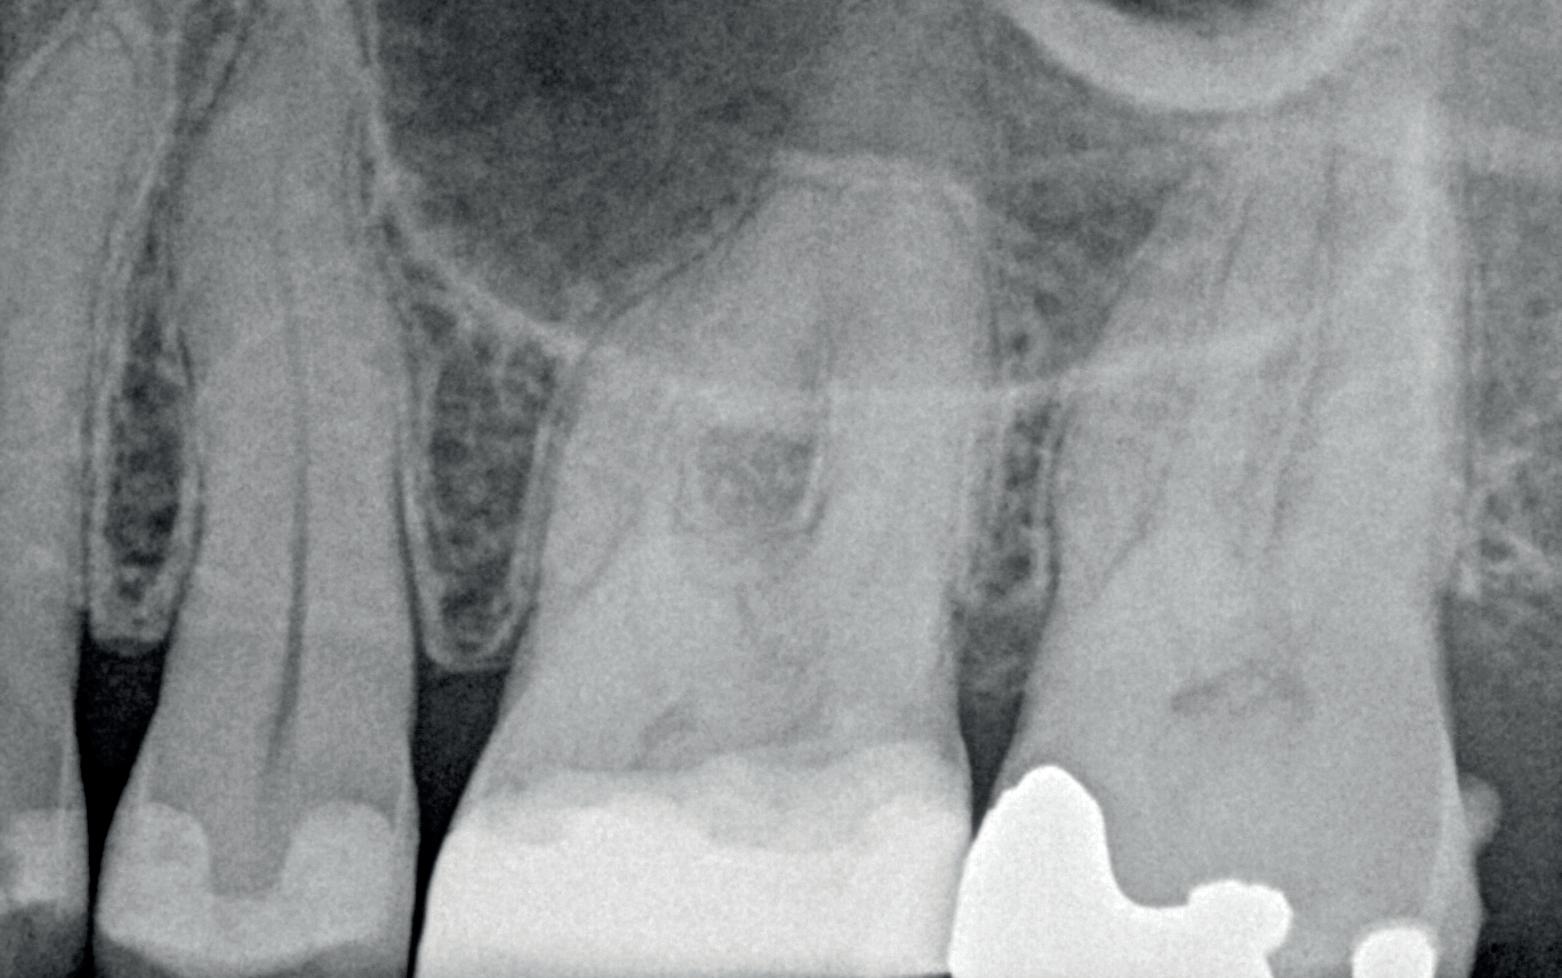

Voordat je aan een wortelkanaalbehandeling begint, zorg je voor (of maak je) een goede beginfoto waar het te behandelen gebitselement volledig op staat afgebeeld. Deze foto geeft essentiële informatie: de grootte van de pulpakamer en de ligging ervan; het aantal en de vorm van de wortels en de breedte van hun wortelkanalen en de lengte van de wortels. Hiermee kan je de DETI-score bepalen en de moeilijkheidsgraad inschatten. De grootte en de ligging van de pulpakamer op de röntgenfoto in combinatie met de ideale anatomische vorm, zoals in foto 1 is aangegeven, bepaalt de uiteindelijke vormgeving van de opening. Bij de molaren liggen de kanaalingangen in de buurt van de knobbeltoppen. Als die niet meer in originele staat

(kroon, restauratie) zijn, kan je ook de wortel gebruiken. Soms moet je net subgingivaal sonderen, maar de kanaalingang ligt in het middel van de wortel. Als je die plek visualiseert en projecteert op je opening, boor je de goede kant op. Nog een tip: wees bij het openen niet spaarzaam met het wegnemen van aanwezig restauratiemateriaal (wees wél spaarzaam met het onnodig wegnemen van tandweefsel).

1. De locatie van de kanaalingangen ten opzichte van de occlusale morfologie (rood). In zwart is de ideale of standaard opening ingetekend. De uiteindelijke vorm van de opening is voorts ook afhankelijk van de klinische situatie, die vooral vanuit een goede begin foto wordt verkregen.

2. Het afgebroken instrument op de foto van de verwijzend tandarts.

3. De opening is vrij klein gekozen. In rood is de ideale opening aangegeven, de tandarts had veel meer restauratiemateriaal mogen wegnemen.